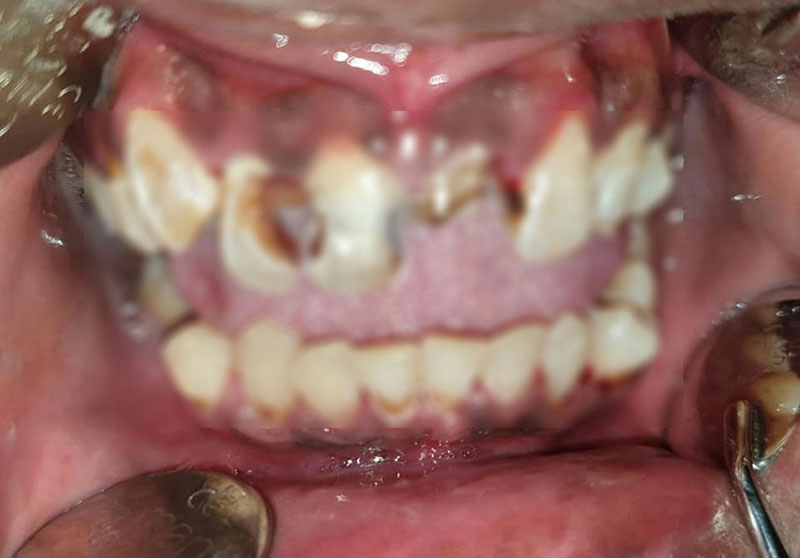

อย่างไรก็ตาม ทางคุณหมอได้โพสต์สภาพฟันหลังจากเอาอุปกรณ์จัดฟันออก ซึ่งสภาพช่องปากดูดีขึ้น พร้อมโพสต์ข้อความเตือนคนที่คิดจะจัดฟันแฟชั่น อยากให้ตระหนักถึงโทษและผลเสียของมันที่มีมากกว่าความสวยงาม